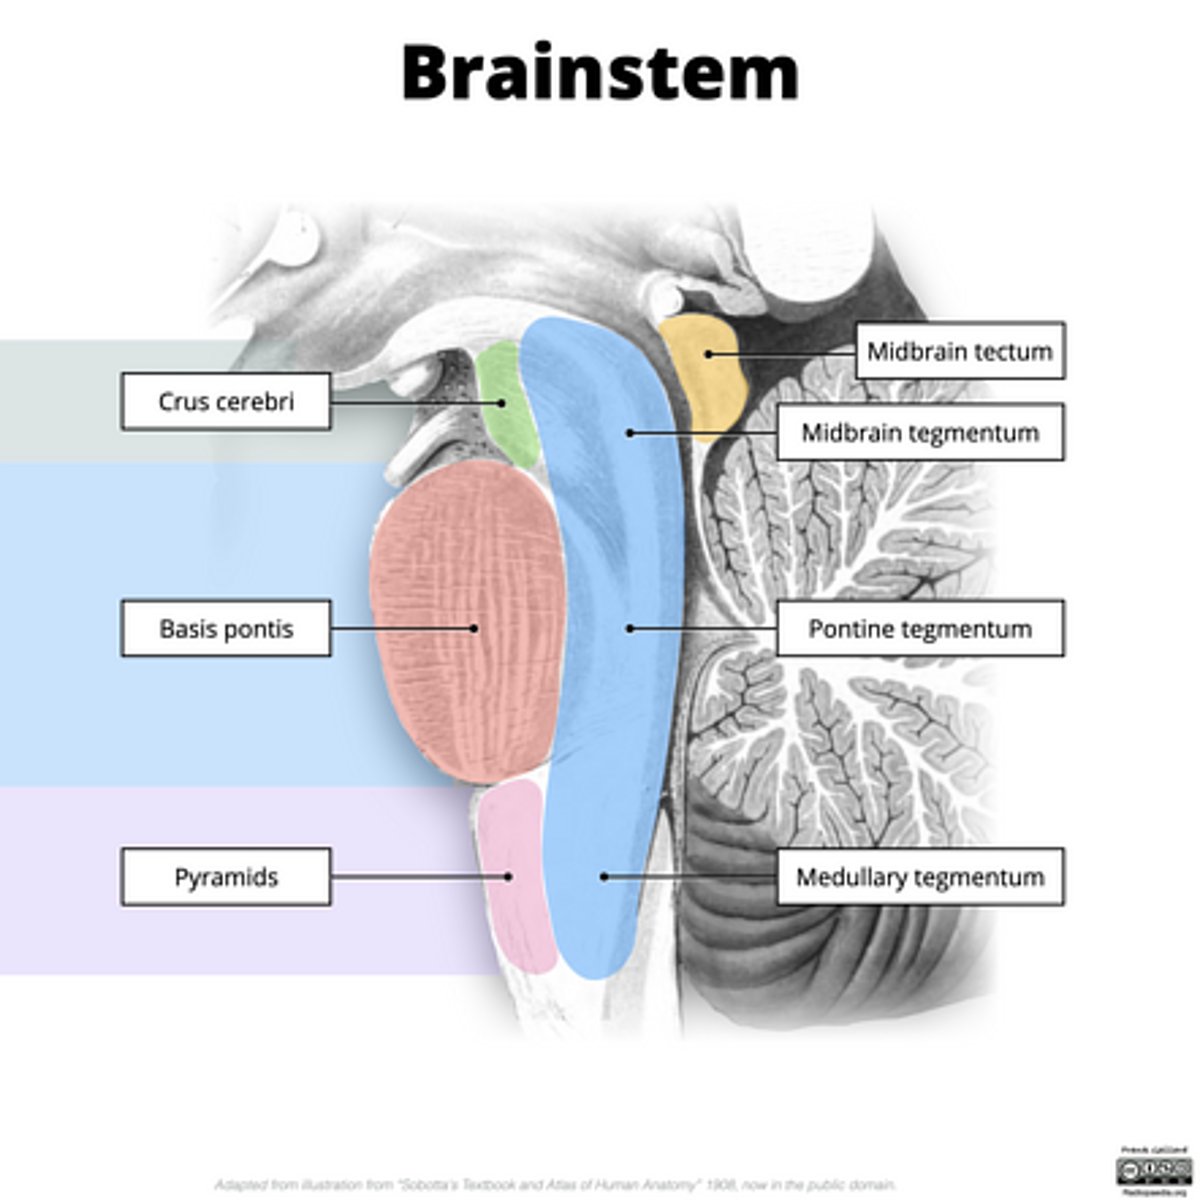

What are the structures of the brainstem?

1. mesencephalon (midbrain)

2. pons

3. medulla oblongata

What is the tectum?

roof of the midbrain

What is the tegmentum?

floor of midbrain

What are the fibers of the tegmentum?

ascending fibers

What is the crus cerebri?

part of the cerebral peduncles which contain descending tracts

What are the fibers of the crus cerebri?

descending fibers

image -- 5